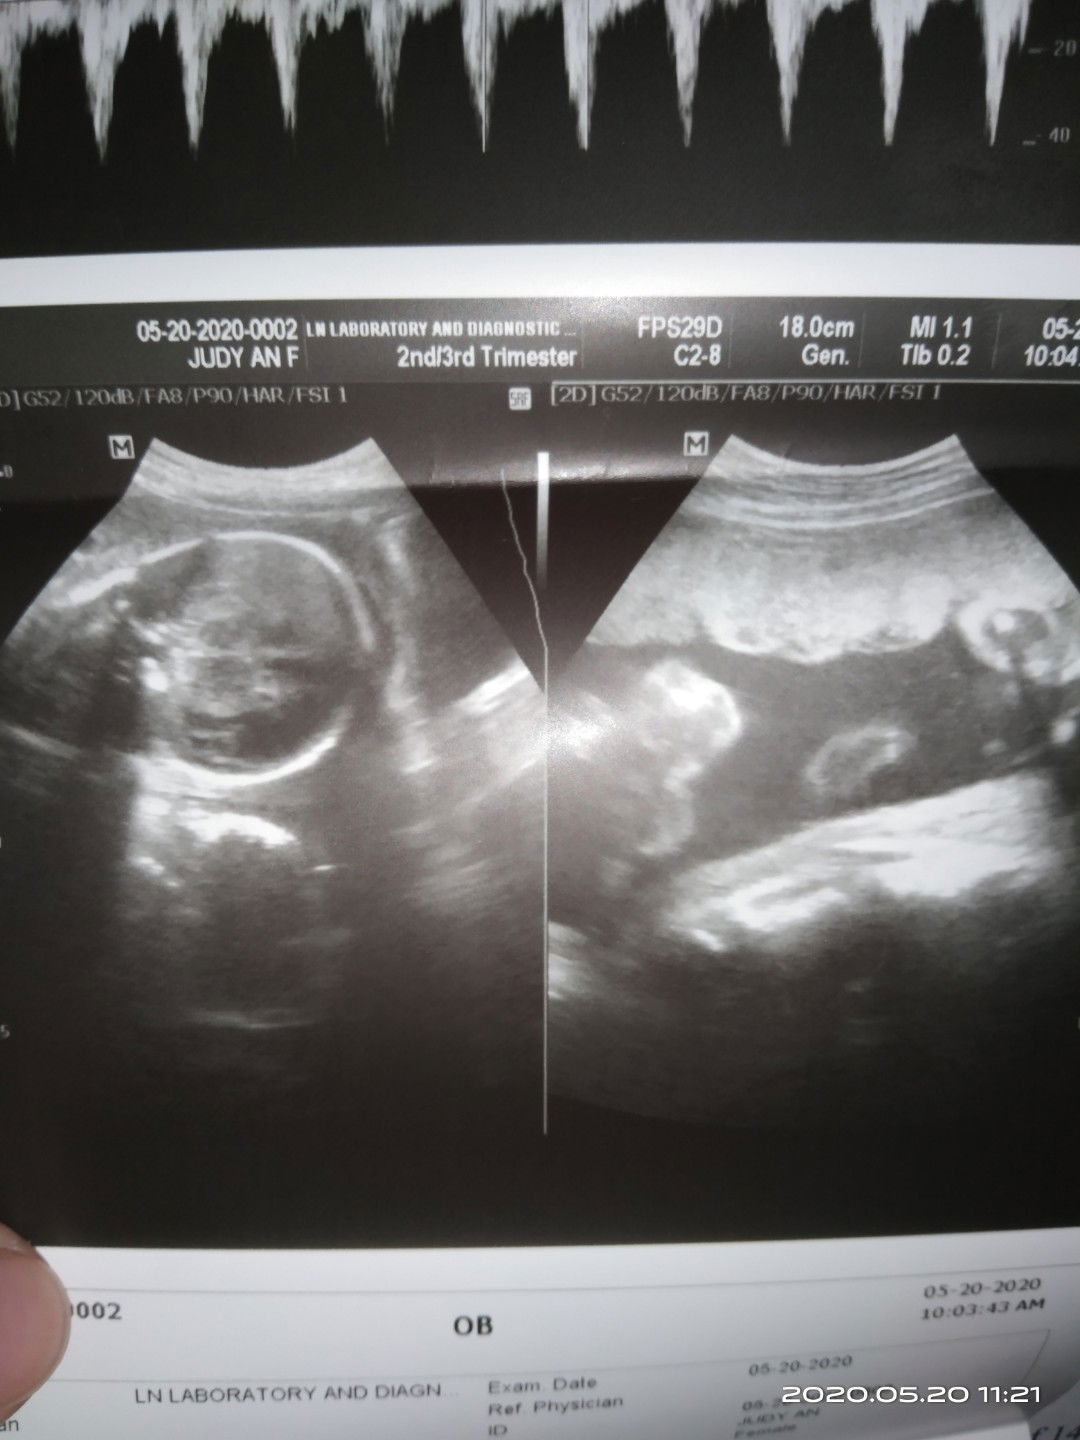

double heart beat ?

possible po kaya na kahit lumabas sa ultrasound ko na isa lang laman ng tiyan ko pero nung nag pa check ako sa lying in samin at nka doppler ako sabi ng ob double heart beat ano po kaya ibig sabihin neto worried po ako at napapaisip kung may mali sa first ultrasound ko although 6 mos na yung tiyan ko nung first ultrasound ko .. share ko lang po baka may same case ako thank you po ftm here ps.nirequired ako na mag pa ultrasound ulit pero mga last week ng july papo ako papa check.